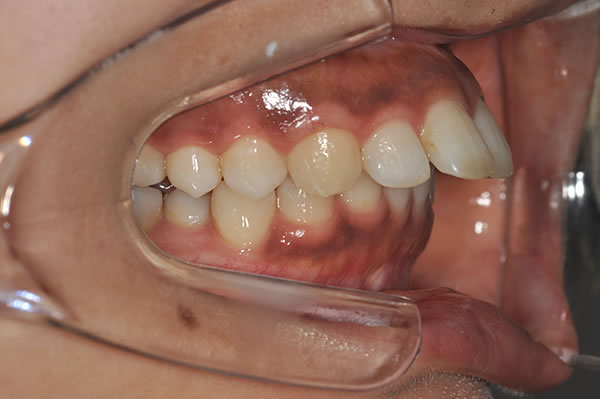

上顎前突症の治療例

上顎前突症(出っ歯)の矯正症例 ケース01

上顎前突症(出っ歯)の矯正症例 ケース02